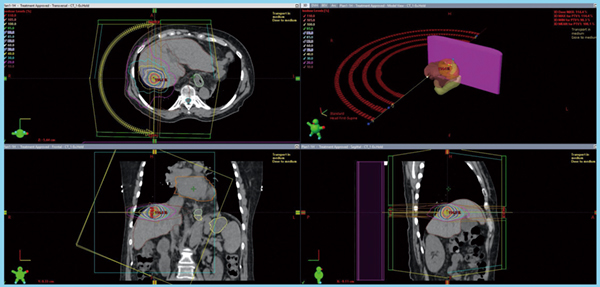

高度なコンピューター技術を使用して、前立腺の患部に集中レベルの放射線を照射します。

SBRT は、医療専門家が前立腺がんの治療に使用できる放射線療法の一種です。この方法では、高エネルギーの集束放射線ビームが前立腺に送信され、高度に標的を絞った放射線の照射が可能になります。

強力で集中した放射線ビームが前立腺の周囲ではなく前立腺のみを標的とするため、医療専門家は従来の治療法よりも迅速に SBRT を完了できます。したがって、膀胱と直腸はそれにさらされません。

治療までの数日間に、前立腺にマーカーを挿入する処置が行われる場合があります。これらは、技師とコンピュータが放射線照射中に治療する正確な領域を特定するのに役立ちます。

医療専門家は、前立腺を検査するために、治療前、治療中、治療後に数種類の画像検査を受けるように指示する場合があります。